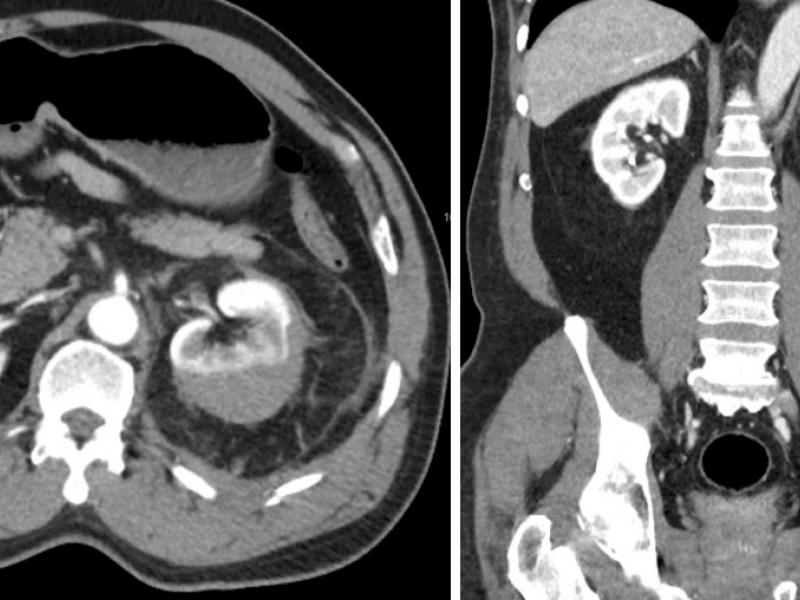

What's the diagnosis?  By Dr. Becca Fieles

A 62 yo. male past history of HTN, CVA, on warfarin presents